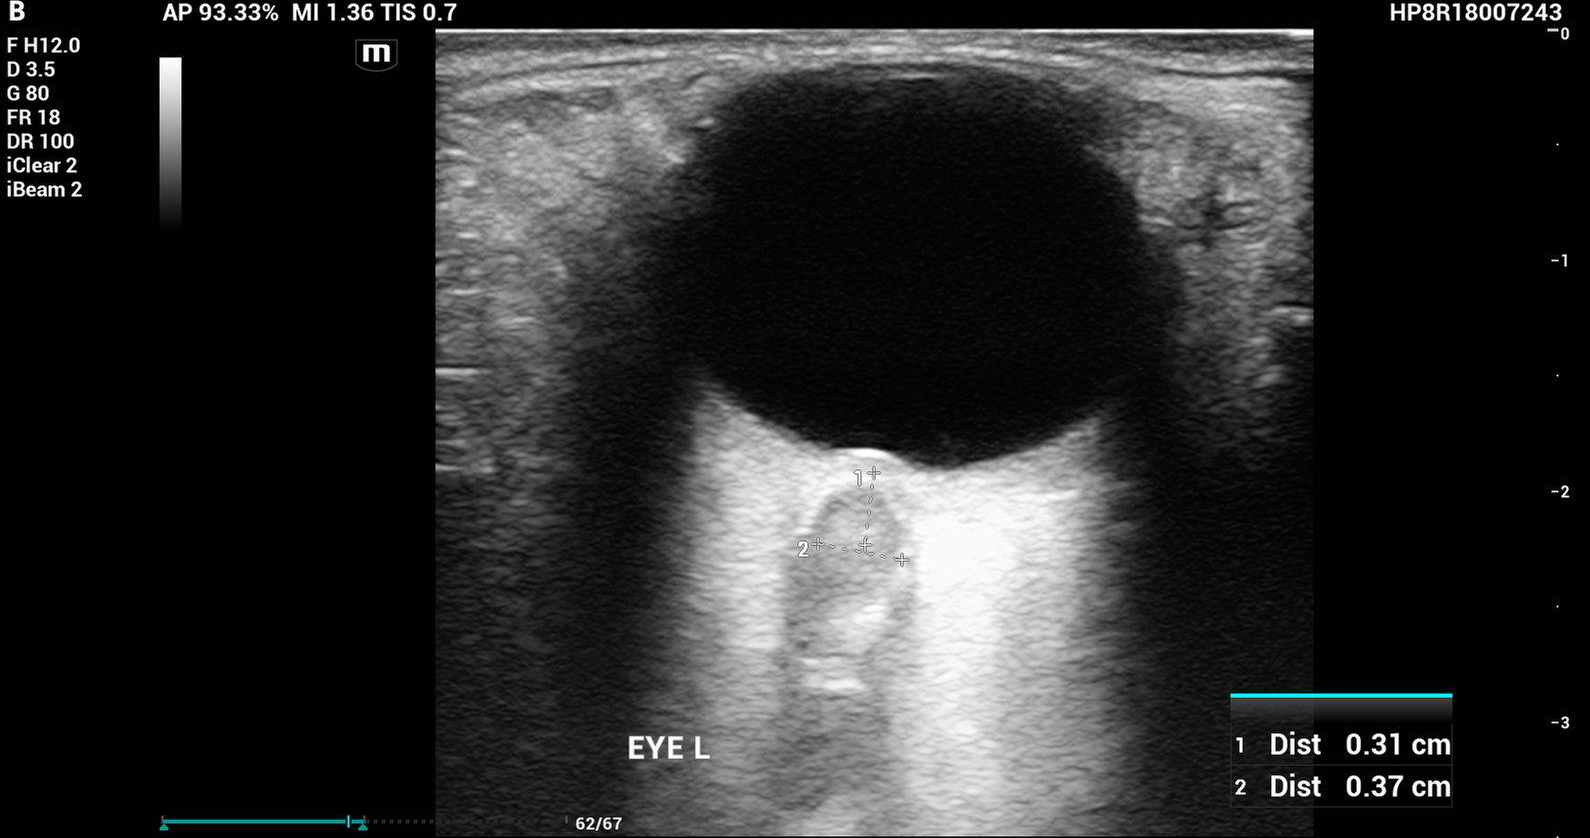

The bedside ultrasound:

Papilledema

Definition: Optic disc swelling due to increased ICP

• Normal IOP with papilledema on ultrasound